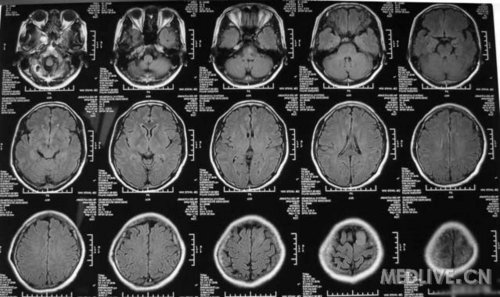

患者女,56岁,因右侧肢体活动不利2天于2011-06-15入院。查体:神志清,精神可,右侧肢体肌力4级,余无阳性体征。CT示左额叶占位,脑膜瘤可能性大。MRI示左额镰旁脑膜瘤,脑干左半亚急性梗塞。给予活血、神经营养、对症治疗,现一般情况好。请高手指点,何时手术切除脑膜瘤好啊?